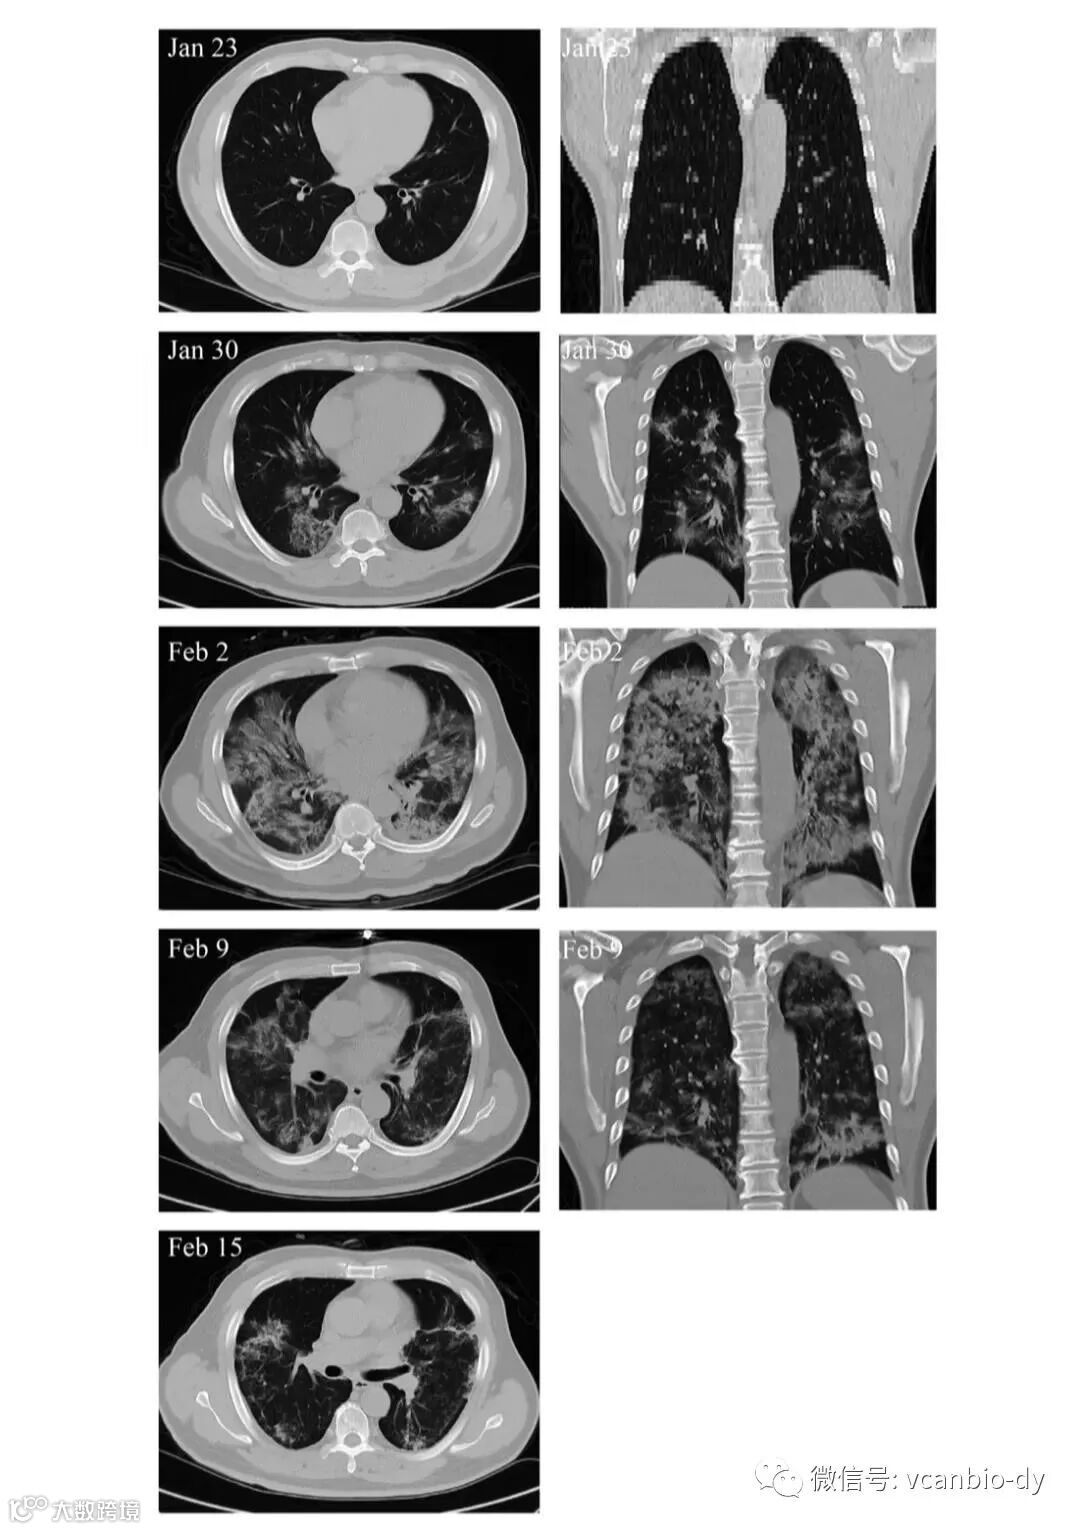

另外,MSC移植能显著加快治疗进程。移植后4天,新冠肺炎危重症患者呼吸频率降至正常范围、发烧和呼吸急促等症状消失。移植后9天,胸部CT成像显示毛玻璃样混浊和肺炎浸润已大大减少。

危重患者肺部影像学显示症状改善